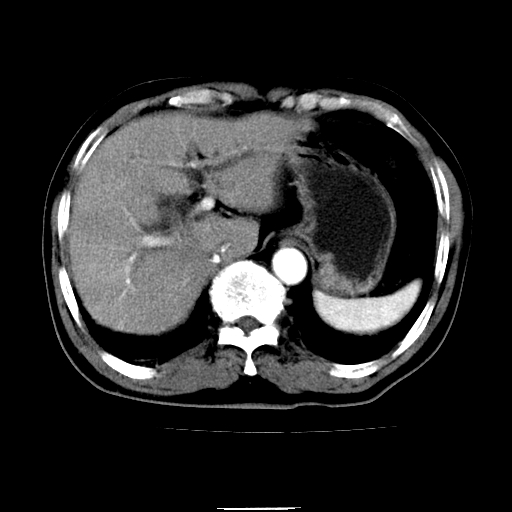

以下是引用chenqiong在2010-3-25 20:56:00的发言:[br]1、胆囊炎,胆囊息肉[br]2、肝内胆管及胆总管扩张,胆总管下端结石[br]3、十二指肠乳头旁憩室

以下是引用zxl51642在2010-3-26 10:47:00的发言:[br]胆囊炎,胆囊息肉,胆总管扩张,但未看到明显肿块,肝内胆管扩张不像恶性,炎性狭窄或阴性结石可能吧,建议mrcp,右肾小囊肿